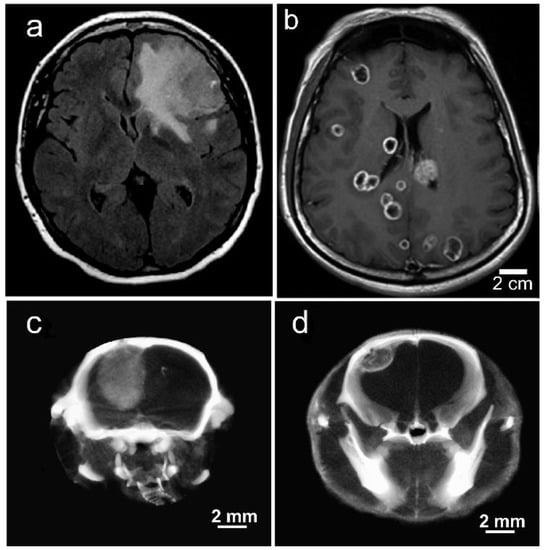

Tumors that metastasize to the brain actually comprise 90% of brain tumors. Metastatic tumors (e.g., lung, breast, and melanoma) grow very differently in the brain compared to gliomas (Figure 15a,b).

Figure 15. Gliomas and metastatic tumors grow differently in the brain as shown by (a) MRI scan of patient with GBM, (b) MRI scan of patient with triple negative breast cancer that has metastasized to the brain, (c) U87 glioma growing in the brain of an athymic mouse, and (d) human triple negative breast cancer growing in the brain of an athymic mouse. (c,d) are microCT X-ray images (70 kVp) 24 h after IV Niodx injection.

Gliomas are highly invasive, expanding and emanating from the origin site. In contrast, metastatic tumors often have multiple contained lesions with well-defined growing edges (Figure 15a,b). Such tumors grown intracranially (IC) in mice showed similar morphologies (Figure 15c,d). They also accumulate Niodx after IV injection and displayed a higher concentration at the growing edge, similar to human brain mets (Figure 15b,d). The intensities seen in the X-ray images are proportional to the iodine concentration. Iodine concentrations were quantified by calibrating the microCT images using iodine standards. The growing edge of the metastatic lesion, such as those seen in Figure 15d, showed an average iodine concentration of 2.9% (w/w) with many peaks at 4.5%. Monte Carlo calculations indicated this could amplify the radiation dose there approximately 5 to 8 times (Table 1).

Table 1. Iodine uptake and calculated Dose Enhancement Factor (DEF) at 72 h after IV injection of 7 g I/kg Niodx for triple negative breast cancer (TNBC) growing in brains of mice. Regions measured: tumor center, tumor growing edge, peak regions of growing edge, expressed as mean ± standard deviation.